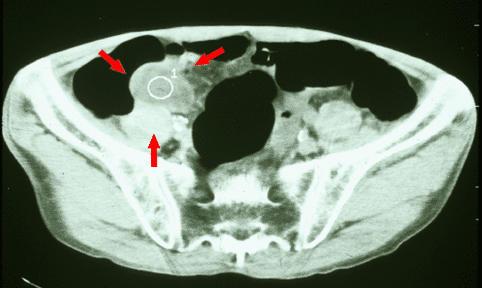

疾病(病理主体)的分类其他肿瘤/恶性阑尾粘液肿瘤

部位(按器官分)大肠/阑尾

检查方法CT

肿瘤最大直径40以上